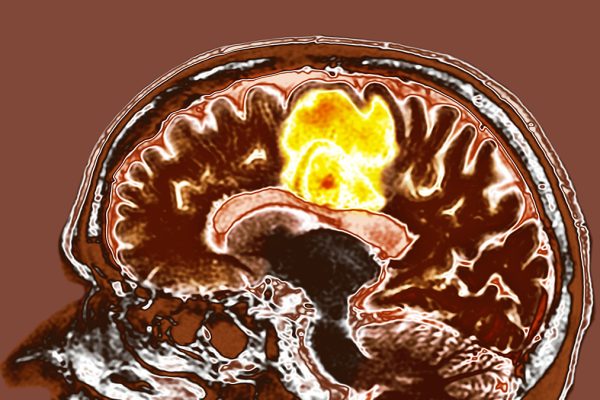

O Combinație Simplă de Suplimente Ar Putea Ajuta la Combaterea Cancerului Mortal al Creierului

Suplimentele sunt resveratrolul și cuprul, ambele cunoscute ca ‘nutraceutice’: extracte din plante sau alimente care se crede că aduc beneficii pentru sănătate. Într-un studiu realizat la Spitalul Tata Memorial din India, 10 pacienți cu glioblastom care se pregăteau pentru intervenția chirurgicală au luat tablete care conțineau atât resveratrol, cât și cupru. Cercetătorii au analizat și…